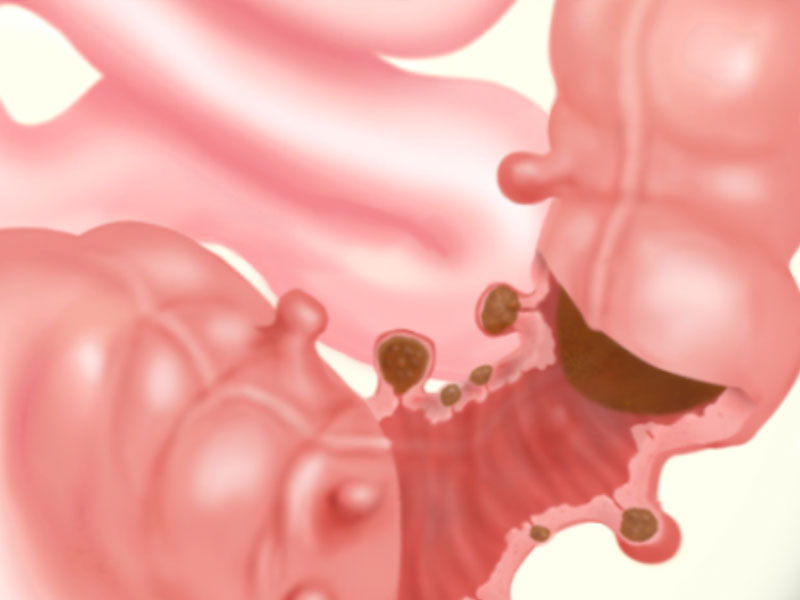

Diverticulitis

Diverticulosis is the formation of Diverticulum, or ‘pouches’ on the bowel. There are two causes: heredity and general wear and tear as we age.